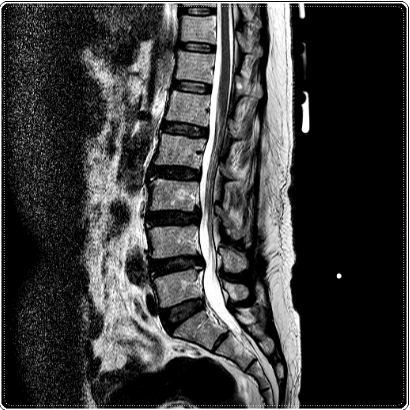

우리 몸은 골반 위에 24개의 척추가 층층이 쌓인 구조입니다.

이 균형이 조금이라도 무너지면 특정 지점에 압력이 몰리고, 그 부위가 쉽게 피로해지죠.

특히 골반 틀어짐, 다리 길이 차이, 거북목, 어깨 비대칭, 측만 같은 문제들이 있으면

요추 3·4·5번에 압력이 집중되는 패턴이 자주 나타납니다.